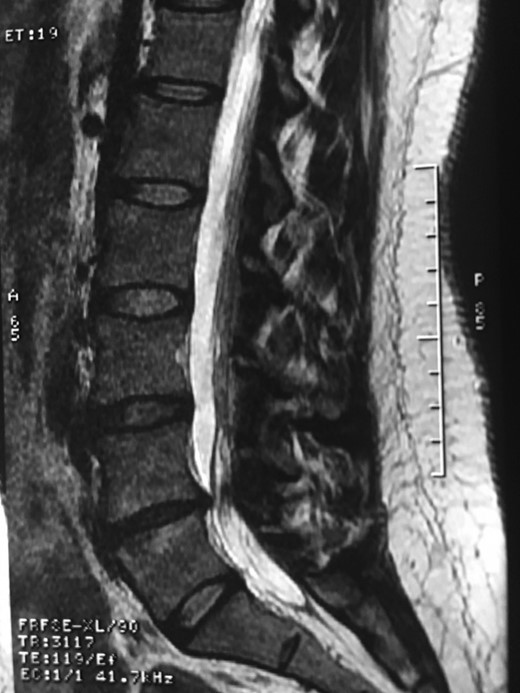

A 42-year-old female presented to the clinic with a history of chronic low back pain. She reported no relevant medical history. She had already been treated in the last 4 years by general practitioners with analgesics and home based physiotherapy with no satisfactory results. She had two previous admissions to the emergency department where morphine was prescribed to control the pain on her lower back. She was under ambulatory treatment with diclofenac, and tizanidine with partial relief of symptoms. Her main complaint was pain on the lower lumbar back with no radiation to the lower extremities. In her physical evaluation she presented limitation to full rotation and bending of the lumbar spine due to pain. Lasegue sign was negative, sensitivity, reflexes, sagittal balance, distal muscular strength and pulses were normal. Radiographs showed an overdeveloped left transverse process of the fifth lumbar vertebra which contacts with the sacrum at the left sacral wing with signs of degeneration at the same site (Fig. 1). Magnetic resonance imaging (MRI) studies were obtained (Figs 2–5). The patient was taken to the operating room where infiltration with 1 mL of lidocaine and 40 mg of Triamcinolone was performed in the pseudoarticulation between the left transverse process and the sacrum under fluoroscopic guidance. She reported a complete relief of pain after the procedure. At three months follow-up she was managed with strengthening and stabilizing exercises for the lumbar spine and postural education was initiated. She remains asymptomatic at her 12 months follow up.

RMN of the patient showing smaller facets in the anomalous articulation and healthy disc compared to the supradjacent one (next figure).

Degenerative changes at the facets and disc in the adjacent segment.

The partial fusion at the lower part of the lumbosacral transition produces important alterations in normal biomechanics at the levels immediately above and below the LSTV. Changes such as hypermobility and abnormal torque moments are present at the level above the LSTV, predisposing it to early degeneration (early disc pathology and facet joint degenerative disease). Restricted movement below the LSTV produces a protective effect against degeneration of disc and facets and is related to changes (facets are smaller and coronally oriented) in the dimensions of the lower level facet joints [7]. These alterations can be verified in the adjacent levels of the LSTV in our patient.